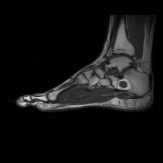

İntraosseöz Ganglion Kisti

Ganglion kisti orta yaş erkeklerde uzun kemiklerin uç kısmında oluşur. Diz, ayakbileği (kalkaneus) ve omuz civarında daha çok görülür. İçi jelöz sıvı ile dolu selim kistlerdir. Tedavi semptomatiktir, mekanik sorun yarattığı zaman cerrahi tedavi gerekebilir, küretaj yeterlidir.

İntra-Osseöz Lipom

Olgun yağ dokusundan oluşan selim bir tümördür. Orta yaş ve üzerindeki hastalarda, sıklıkla kalkaneusda ve bazı uzun kemiklerde ortaya çıkar. Düzgün sınırlı, radyolojik olarak yağ görüntüsü veren lezyonlardır. Biyopsi nadiren gereklidir. İntraosseöz lipomların çoğu tesadüfen tespit edilir. Genelde takip yeterlidir. Rahatsızlık veren olgularda cerrahi tedavi gerekebilir. Tedavisi, cerrahi olarak çıkartılıp yerine kemik doldurulmasıdır. MRI’da tüm sekanslarda hemojen görüntü var ise biyopsi yapmadan cerrahi tedavi yapılabilir.